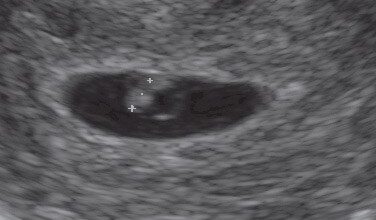

Ecografía con 3 semanas: el saco gestacional mide 7 mm de diámetro.